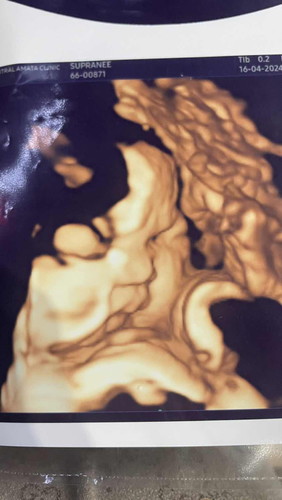

บ้านนี้37+4น้ำหนักน้อง3100กรัมแล้วค่ะ วันที่4/4หมอนัดผ่าแล้วค่ะ ตอนนี้สู้ๆก่อนนะค่ะอาการนอนไม่หลับ ปวดหน่วงไปหมดค่ะตอนนี้

ดูจากอัลตร้าซาวด์ นน.น้องน่าจะมากกว่านี้ จ้ำม่ำน่ารักมากเลยค่ะ อีกนิดเดียวก็ได้เห็นแล้ว สู้ๆค่ะ